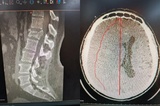

Перелом позвоночника, черепно-мозговая травма, гематома: на выходных в районной больнице провели сложные операции